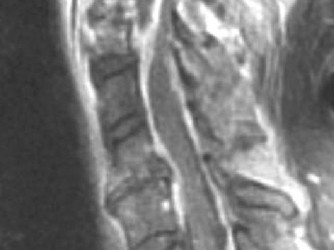

CASE 1 A 63-year-old male sustained a hyperextension injury to his neck while diving into a pool. Upon presentation, he reports decreased sensation in his hands and decreased strength in his arms and wrists, but no lower extremity complaints. On motor examination, he has 5/5 strength in his deltoids and elbow flexors and 4/5 strength in the elbow extensors, wrist extensors, and finger flexors. Lower extremity motor examination is normal. Sensation is decreased to light touch in both hands. Otherwise his sensation is preserved. Images of his cervical spine are shown in Figures 1–1 to 1–3.

Figure 1–2

The correct answer is (B). The clinical scenario describes a patient with central cord syndrome (CCS). CCS continues to be the most common incomplete spinal cord injury accounting for 15.7% to 25% of all spinal cord injuries. The characteristic presentation is an extension moment injury in a previously spondylotic and stenotic spine. Figures 1–1 to 1–3 demonstrate a spondylotic spine with central narrowing and CSF effacement that is worst at the C3–4 level. Bleeding, edema, and/or Wallerian degeneration lead to damage of the lateral corticospinal tract which is the main descending motor tract in the spinal cord. The more central anatomic position of the homunculus to the upper extremities places them at greater risk than those to the lower extremities. As such, injury to the lateral corticospinal tract is characterized by upper more than lower extremity involvement and motor deficits being more pronounced than sensory deficits.